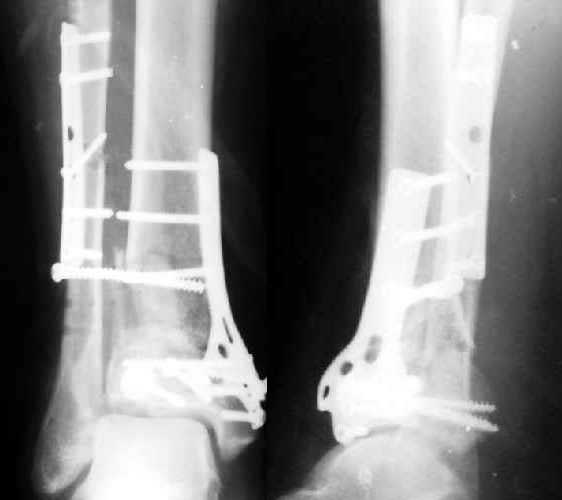

Итог операции Через 1,5 месяца

Полтора месяца назад мужчине 45 лет выполнена открытая репозиция дистального отдела большеберцовой кости и внутренняя фиксация (снимок 1).

На другой ноге - переломы нескольких плюсневых костей. Из-за сопутствующих урологических проблем через две недели перевели в другое учреждение, там был вынужден ходить с костылями с нагрузкой на обе ноги. При контрольной явке к нам через месяц обнаружилась несостоятельность фиксации (снимок 2). Какие выходы их положения можно тут предложить?